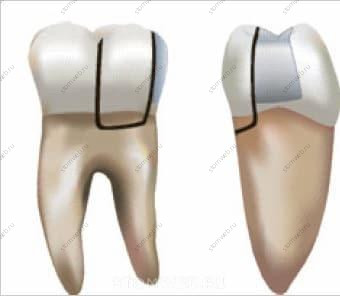

Коронка и корень являются не только местом начала, но и областью основного повреждения. На коронке (в большинстве случаев при распространении на корень) выделяют перелом бугра, перелом зуба и раскол зуба (Рис. 2 и 3);

Рис. 3. Переход перелома зуба в раскол зуба. (A) Перелом зуба: перелом идёт в мезиодистальном направлении на коронковой части и встречается в нереставрированных зубах или тех, которые имеют небольшие реставрации; располагается на коронке зуба и может распространяться на корень. (В) При осмотре с проксимальной стороны перелом располагается центрально, а глубина его распространения на корне варьируется; фрагменты зуба не отделяемы. (С) Раскол зуба: перелом идёт в мезиодистальном направлении на коронковой части и является результатом распространения/роста перелома зуба; располагается на коронке зуба и распространятся на корень. При осмотре с проксимальной стороны перелом располагается центрально и распространяется глубоко на вестибулярную или оральную поверхность корня; обычно фрагменты зуба отделяются.

переломы, ограниченные корнем, называются вертикальными переломами корня (Рис. 4).

Рис. 4. Вертикальный перелом корня. Зачастую перелом распространяется в вестибулооральном направлении на корне и встречается в зубах, на которые воздействовала нагрузка во время компакции обтурационного материала или во время установки штифтов. Располагается на любом уровне корня. При осмотре с вестибулярной или язычной сторон, перелом может начинаться на или в корне и распространяться коронально по направлению к пришеечному краю. Фрагменты зуба могут как отделяться (полный перелом, вовлекающий две поверхности корня), так и не отделяться (неполный перелом, вовлекающий одну поверхность корня).

Термин “трещина” подразумевает частичное разрушение структуры материи (такой, как чайная чашка, зуб и т.д.). Термин “перелом” означает полное или частичное разрушение структуры материи (той же чашки, зуба, кости и т.д.). Healthline.com утверждает, что если на кость оказывается большее давление, нежели она способна выдержать, произойдёт её раскол или разрушение. Поэтому термины “перелом бугра” и “вертикальный перелом корня” означают частичное или полное разрушение зубов; “трещина” и “перелом зуба” - только частичное разрушение зубов (нет отделяющихся фрагментов); “раскол зуба” - только полное разрушение зубов (есть отделяющиеся фрагменты) (Рис. 1).